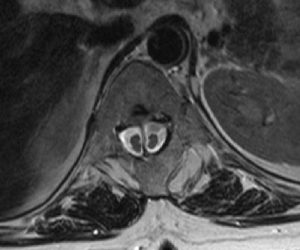

Omurilik tümörleri omurga ve omuriliği oluşturan kemiklerde, sinirlerde veya diğer yumuşak dokularda oluşabilir. İyi veya kötü huylu olabilirler ...

Bifid kord, ayrık omurilik sendromu da denen bu tablo, yani diastematomyeli yarık omurilik anlamına gelir. Genellikle omurga kemiğinin ...

Omurilik Yaralanmaları Omurilik yaralanmaları, omurganın içinde bulunan sinir dokusunun, travma ya da başka nedenlerle oluşan yaralanmaların ...